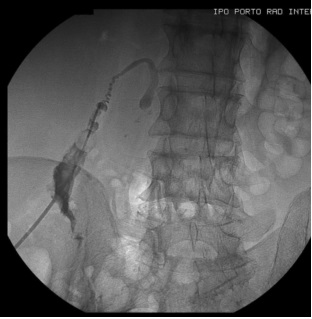

经胆囊胆道支架植入术